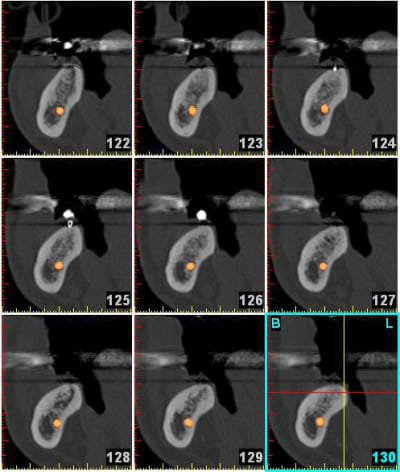

voici le cas extraction en décembre 2011 ce qui me pose problème c'est le 2eme implant le 8 mm passe mais le col ne serait pas enfoui , ne vaut il donc pas mieux plus enfouir un 6 mm d'où ma question.

L'os dans le 2 eme site est type 4 et type 3 vers le fond et avec le 8 mm je me retrouve dans la corticale linguale

Mes premiers implants courts: Que des implants courts! Pas assez de recul (2 ans) de plus on voit que celui en 27 n'a pas été enfoui j'ai laissé le col dépassé ( voulait pas qui parte dans le trou trou).

A toi de voir si ça t'aide. Ok je n'avais pas de contrainte d'axe prothétique (grace au système)mais bon ça renseigne un peu.

Quelle taille ??? Dans mon etude on peut placer un 10*4.2 mm en avant et un 6*5 mm en arriere le tout lié....Vous en pensez quoi?

sinon le deuxième site, moi, me paraît louche...c'est pas du D4, j'aurais plutôt tendance à dire que c'est du tissu de granulation...( et peut être bien un petit morceau de racine...c'est pas très net...)

une racine le morceau en distal e je l'ai enleve avant le scan, la radio date du 21.1 et le scan du 14.3.... je ne pense pas avoir de pano d'ensemble post extractionnel.

oui, donc tu es à 8 semaines post extraction pour ton scan...c'est un peu juste pour juger de la densité osseuse, non?

le problème: tu es limite en hauteur, et si tu es dans du mou, çà va pas vraiment le faire pour trouver une stab primaire...

perso, je laisserais çà tranquille encore 1 mois ou 2, pano de contrôle et si ok, on plante...

et non pas à 8 semaines je l'ai extraite le 19.11.2011 donc c'est plus et je te joins une retro avant l'extraction la dent ne présentais pas de lésion paro enorme donc je ne vois pas pourquoi un TG se serait développé plus facilement.

à 4 mois amha çà devrait être plus dense si tout était normal...

A mon avis aussi et maintenant quelles solutions mis à part un implant court ou une greffe qui a des chance de rater (les 2 que j'ai fais faire n'ont pas pris) et les exclusifs sur Marseille (qui font partie des pointures nationales) préfèrent de leur avis des implants court (7mm chez Nobel) plutôt que des greffes.

a mon avis, sur la 2eme zone d'implant, t'es dans de la soupe! tu vas au casse-pipe si tu plantes...(j'ai déjà eu ce genre d'image et conclusion...)

la lacune semble bien délimitée par des parois, donc tu peux tenter: ouverture curetage et comblement.